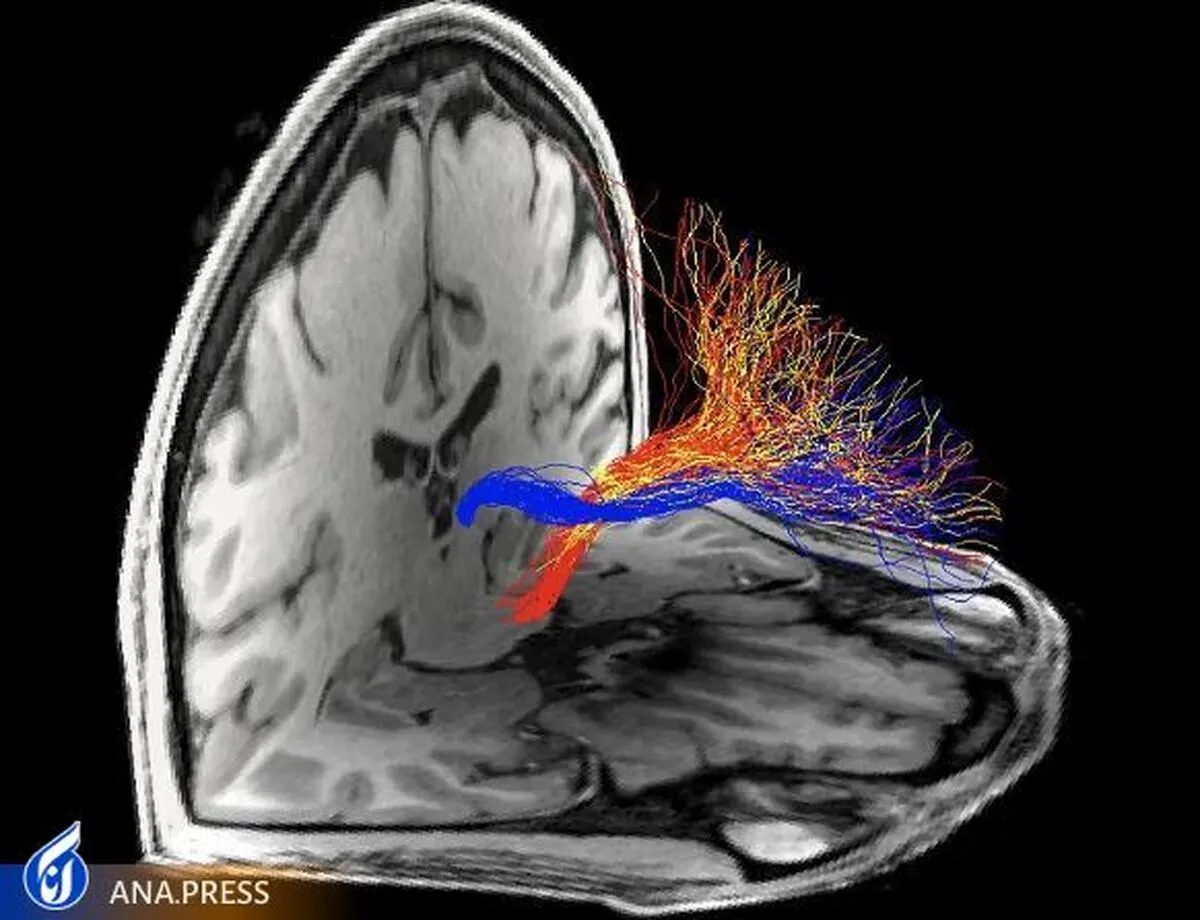

اتصالات ساختاری با قشر جلوی پیشانی که از هستههای هدف قرار گرفته در زیر قشر (آبی: هابنولا، زرد: تالاموس قدامی، قرمز: ناحیه تگمنتال شکمی) مدلسازی شدهاند با استفاده از تراکتوگرافی MRI انتشاری. خواص ریزساختاری مجرای هابنولا به طور منحصر به فردی در افراد مبتلا به اختلال مصرف کوکائین یا هروئین کاهش یافت. نتایج، ویژگی بالقوه اتصالات قشری پیش پیشانی متمایز را به آسیب شناسی عصبی اعتیاد به مواد مخدر برجسته میکند.

برای اولین بار در مغز انسان، تیمی از دانشمندان از تصویربرداری رزونانس مغناطیسی انتشار (MRI) برای بررسی ویژگیهای ریزساختاری مدار PFC-habenula در افراد مبتلا به کوکائین یا هروئین در مقایسه با شرکتکنندگان سالم استفاده کردند. دستگاه امآرآی انتشاری از تصویربرداری غیرتهاجمی مغز برای مدلسازی بستههای فیبر در مغز انسان زنده استفاده میکند.